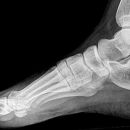

Fuß streng seitlich

Komplexe anatomische Verhältnisse => Zusätzlich a.p.- und schräge Aufnahme oder Vergleichsaufnahmen der Gegenseite anfertigen! Komplexen Luxationen/ Frakturen => großzügige CT-Indikation! Zentrale Kalkaneusfrakturen (vgl. Kalkaneus) => absolute CT-Indikation! Isolierte Frakturen des Os naviculare, der Ossa cuneiforma oder des Cuboids sind Raritäten => Immer nach zusätzlichen Verletzungen (Calcaneus, Talus, OSG,...) suchen!

Beurteilungskriterien

• Korrekte Stellung, kongruente Gelenkflächen?

• Klassisches Zeichen zentraler Kalkaneusfrakturen in der seitlichen Aufnahme: Abflachung des BÖHLER- Tubergelenkwinkels, physiologisch 25-40° (vgl. Kalkaneus seitlich)

• "target areas" subtiler Frakturen: Talushals, Proc.posterior tali, Proc.lateralis tali, Proc.ant.calcanei, Sustentaculum, Entenschnabelfraktur (knöcherner Ausriß des Ansatzes der Achilllessehne), Tuberositas ossis metatarsalis V!!!

Cave:

• akzessorische Knochen und Normvarianten der Apophsenentwicklung Wachstumsalter (vgl. a.p.-Aufnahme)

• Ermüdungsfrakturen initial oft nicht erkennbar => Röntgenkontrolle in 8-10d.